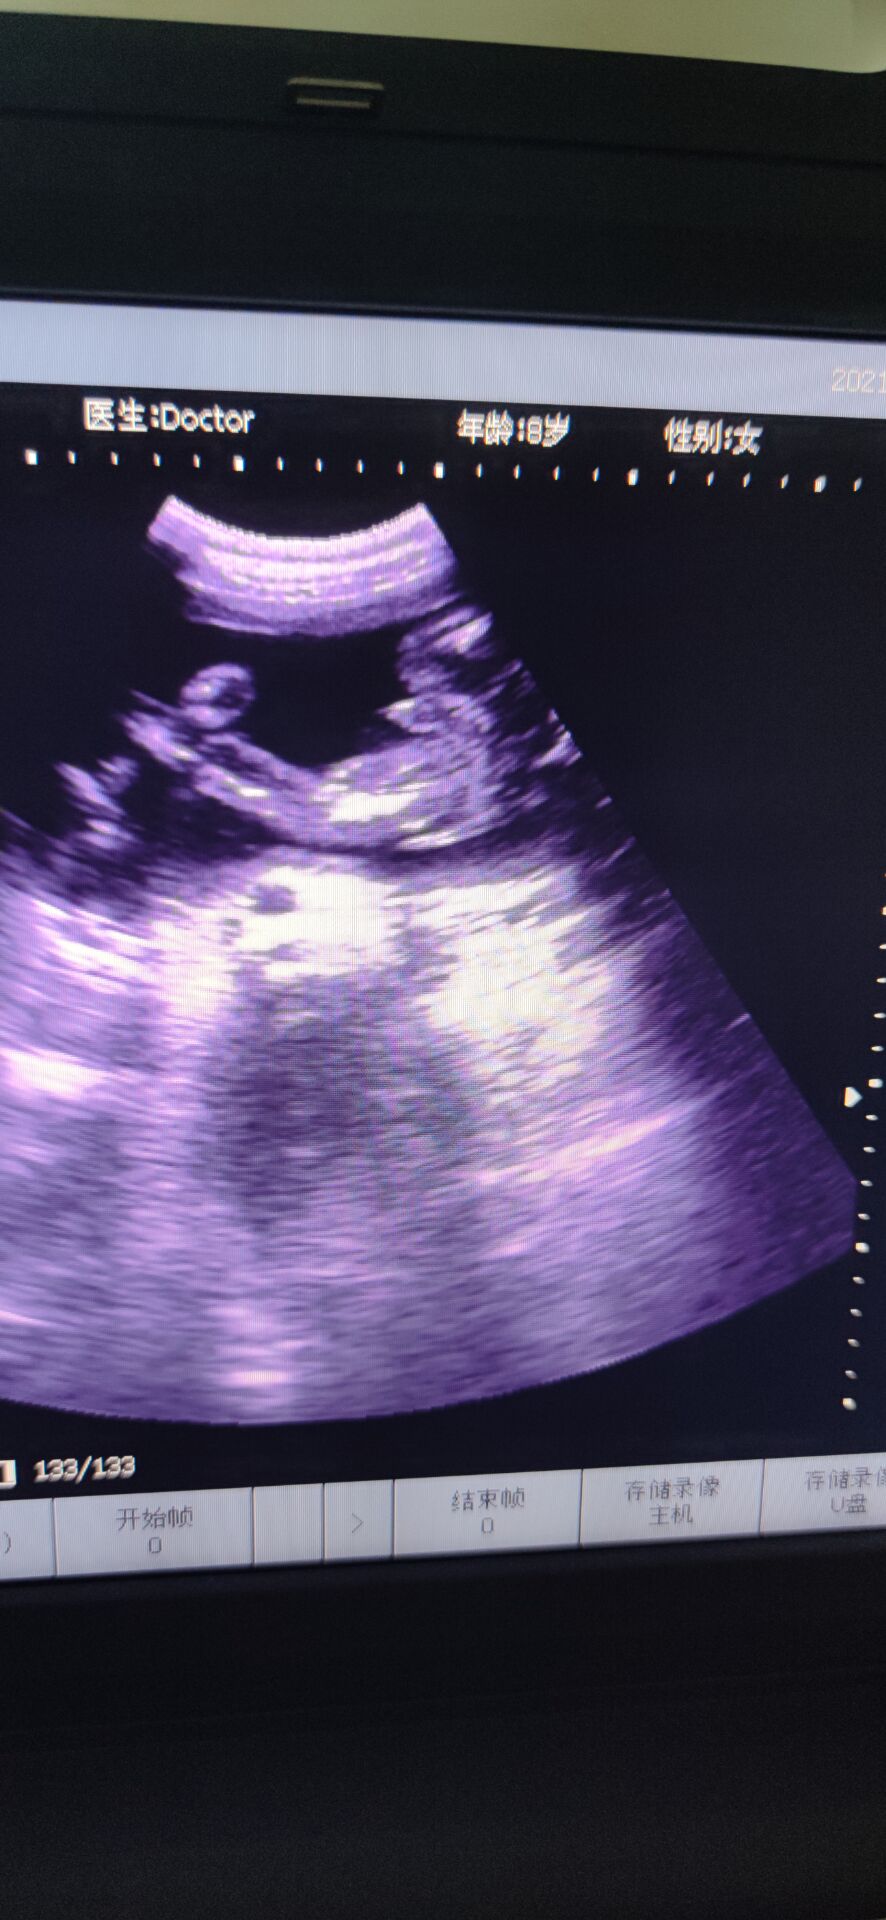

6月5日下午,分泌物有点血丝,而我在洗碗的时候,小腹有点点坠痛,但是休息下能缓解,到了晚上跟孕妇群的人聊了聊,不放心,挂急诊,B超做了好久,突然医生让我别动,就躺着,说:“你宫口已经开了,内宫口全开了,外宫口开了两指了,羊膜在阴道里,都快到阴道口了!”听到的那刻,突然就心慌紧张了,整个人都在发抖,腿也控制不住地抖,才26周啊,还没足月。产科的人立马下来把我拉到待产室内检,然后跟我说还没足月,什么都还没发育好,生下来就要立马进保温箱,要生下来起码得准备一百万…说了很多,大概意思都是劝我引产,可是我舍不得啊,我下不定决心,她们就破例让我老公进来,同样地话跟我老公说了一遍,但是我们想保,医生就给了建议,转入市人民医院,那里有紧急环扎术,当天晚上就转过去,中途医生给我上了抑制宫缩的药。转过去的时候已经是凌晨两点多了,医生说她们医院已经不做紧急环扎术了,她也不知道哪个医院能做,而且这么晚了,我再转院也是折腾,我这才26周,产科和妇科不会收的,只能收计划生育科,但是计划生育科是不会管我的,因为我这情况医学上说就是难免流产,打完从上一个医院带来的吊瓶后,是不会管我的,顺其自然。这不是我们想要的答案,医生说没有其他办法,我们也不知道该怎么办,想着先转计划生育科吧,当晚做的核酸,但是因为核酸报告没那么快出,所以把我放到了抢救室,期间打了一枚促肺针。那晚好煎熬啊,睡又睡不着,周围都是打吊瓶的人,临急出的门,手机又没什么电,又不敢乱动,躺的身子僵硬疼痛,又不能下床走动,老公给我买了包护理垫,上厕所就直接尿在护理垫上。好不容易熬到早上,核酸报告还没出,到了十点多也没出,我老公在网上查资料,打电话,看哪个医院可以做紧急环扎,他侧对着我坐着,我看到他哭了,默默在流泪,那时候真心疼他。好不容易市妇幼说她们医院可以做,但是不派车来接,人民医院也不派车送。怎么办呢,叫出租车吗?可是出租车会愿意拉我吗而且我还得躺着。我老公和我家公就出去联系私人救护车。出去了好久,我就躺在床上望着门口,一有人进来,我就以为是他们回来了,但是不是,是别的病人的家属,后来我借别人手机给他打电话,我说:“你不要离开太久,我一个人在这,我害怕[泣不成声]”我老公他们好不容易联系到私人救护车把我送到市妇幼,内检时医生说做不了紧急环扎了,我已经有宫缩了,只能打吊瓶,抑制宫缩。因为疫情原因,只能一个陪护,我老公做的核酸还没出报告,要明天才能出,所以临时请了个月嫂陪护我,那天已经是6月6日了,晚上睡觉的时候感觉尿尿那里湿湿的,一擦,有血丝,而且不是一点点,叫了医生,医生给我上了另一种抑制宫缩的药,没一会就心跳加速,医生说那药是会让心跳加速,还让我如果有宫缩要告诉她。那一整晚都睡不安稳,一整晚,时间才过去五分钟,感觉太难熬了。等到6月7日中午,我老公的核酸报告出来了,他终于可以进来陪护了,心里开心了一些,做了B超,显示是26+6周,980克。因为我们要保,所以儿科医生也过来跟我们说了些关注事项和风险,还安慰我说,我这孕周和宝宝体重也还好,她们治疗过很多早产儿,百分之九十都能健康平安出院,让我不要太担心。